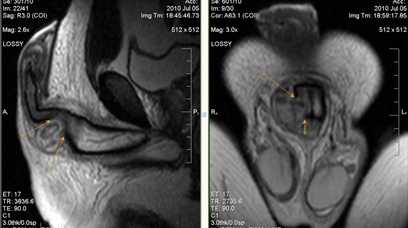

Визуализируются кавернозные тела, окруженные белочной оболочкой (головки стрелок), спонгиозное тело (*) и артерии кавернозных тел (изогнутые стрелки).

Травма полового члена

Определяется нарушение целостности правого кавернозного тела и разрыв окружающий его белочной оболочки (стрелки) с формированием подкожной гематомы –«перелом» пениса.

Болезнь Пейрони

Происходит поражение соединительной ткани с формированием фиброзных локальных утолщений белочной оболочки полового члена и внутрикавернозных перегородок. Синонимы: фиброзный кавернит, пластическая индурация полового члена.

Определяется дорзальная индурация белочной оболочки, значительная дорзальная деформация пениса. Стрелки показывают значительное фокальное утолщение дорзальных отделов белочной оболочки (больших размеров бляшка).